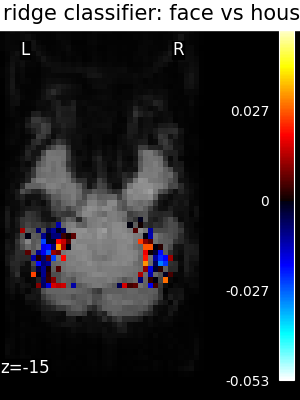

The ridge is fast to fit and cross-validate, but it will not work well on ill-separated classes, and, most importantly give ugly weight maps

The corresponding weight maps (below) differ widely from one estimator to the other, although the prediction scores are fairly similar. In other terms, a well-performing estimator in terms of prediction error gives us little guarantee on the brain maps.